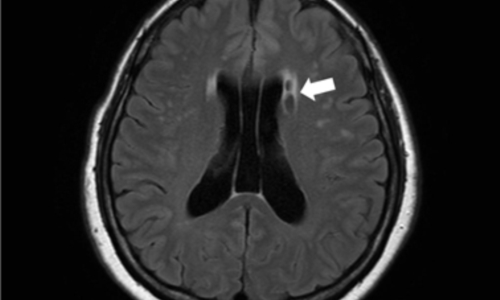

뇌경색 원인은 동맥경화증으로 시작합니다. 병이 든 혈관 어떤 곳에든 핏덩어리가 생겨나면 심장에서 뇌로 흐르는 혈액의 흐름을 방해하게 됩니다. 만약 핏덩어리가 내경동맥이나 뇌혈관을 막게 되면 치명적인 뇌 손상을 입을 수 있습니다. 이렇듯 갑자기 혈관을 막는 경우도 있으나, 혈전에 의하여 점차 혈관 너비가 좁아지면서 허혈성 뇌졸중이 유발되는 경우도 있습니다.

뇌졸중에서도 혈관이 막히는 뇌경색이야말로 촌각을 다투는 응급질환이라고 볼 수 있습니다. 뇌혈관이 막히면서 점차 뇌세포가 괴사하기 때문에, 증상 발현 3시간 안에 혈전용해제를 투여하고 시술에 들어가야 심각한 상황을 면할 수 있습니다. 뇌경색 치료방법에 있어 가장 중요한 것은 혈전을 녹이는 혈전용해제를 정맥 투여함으로써 막힌 혈관을 뚫어주는 것입니다. 하지만 혈전용해제의 경우도 출혈 가능성이 있는 환자에게는 투여할 수 없으며, 또한 혈소판 수치가 낮아서 지혈이 되지 않는 경우에는 제외된다고 합니다.